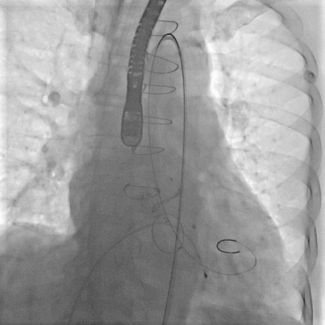

跨瓣建立轨道

主动脉瓣架植入

根据造影情况决定选择VenusA 23号瓣膜

主动脉瓣架释放

复查造影

跨瓣压差下降为20左右,超声复查微量瓣周漏,瓣膜植入位置良好,遂闭合入路送回病房,一周后康复出院。